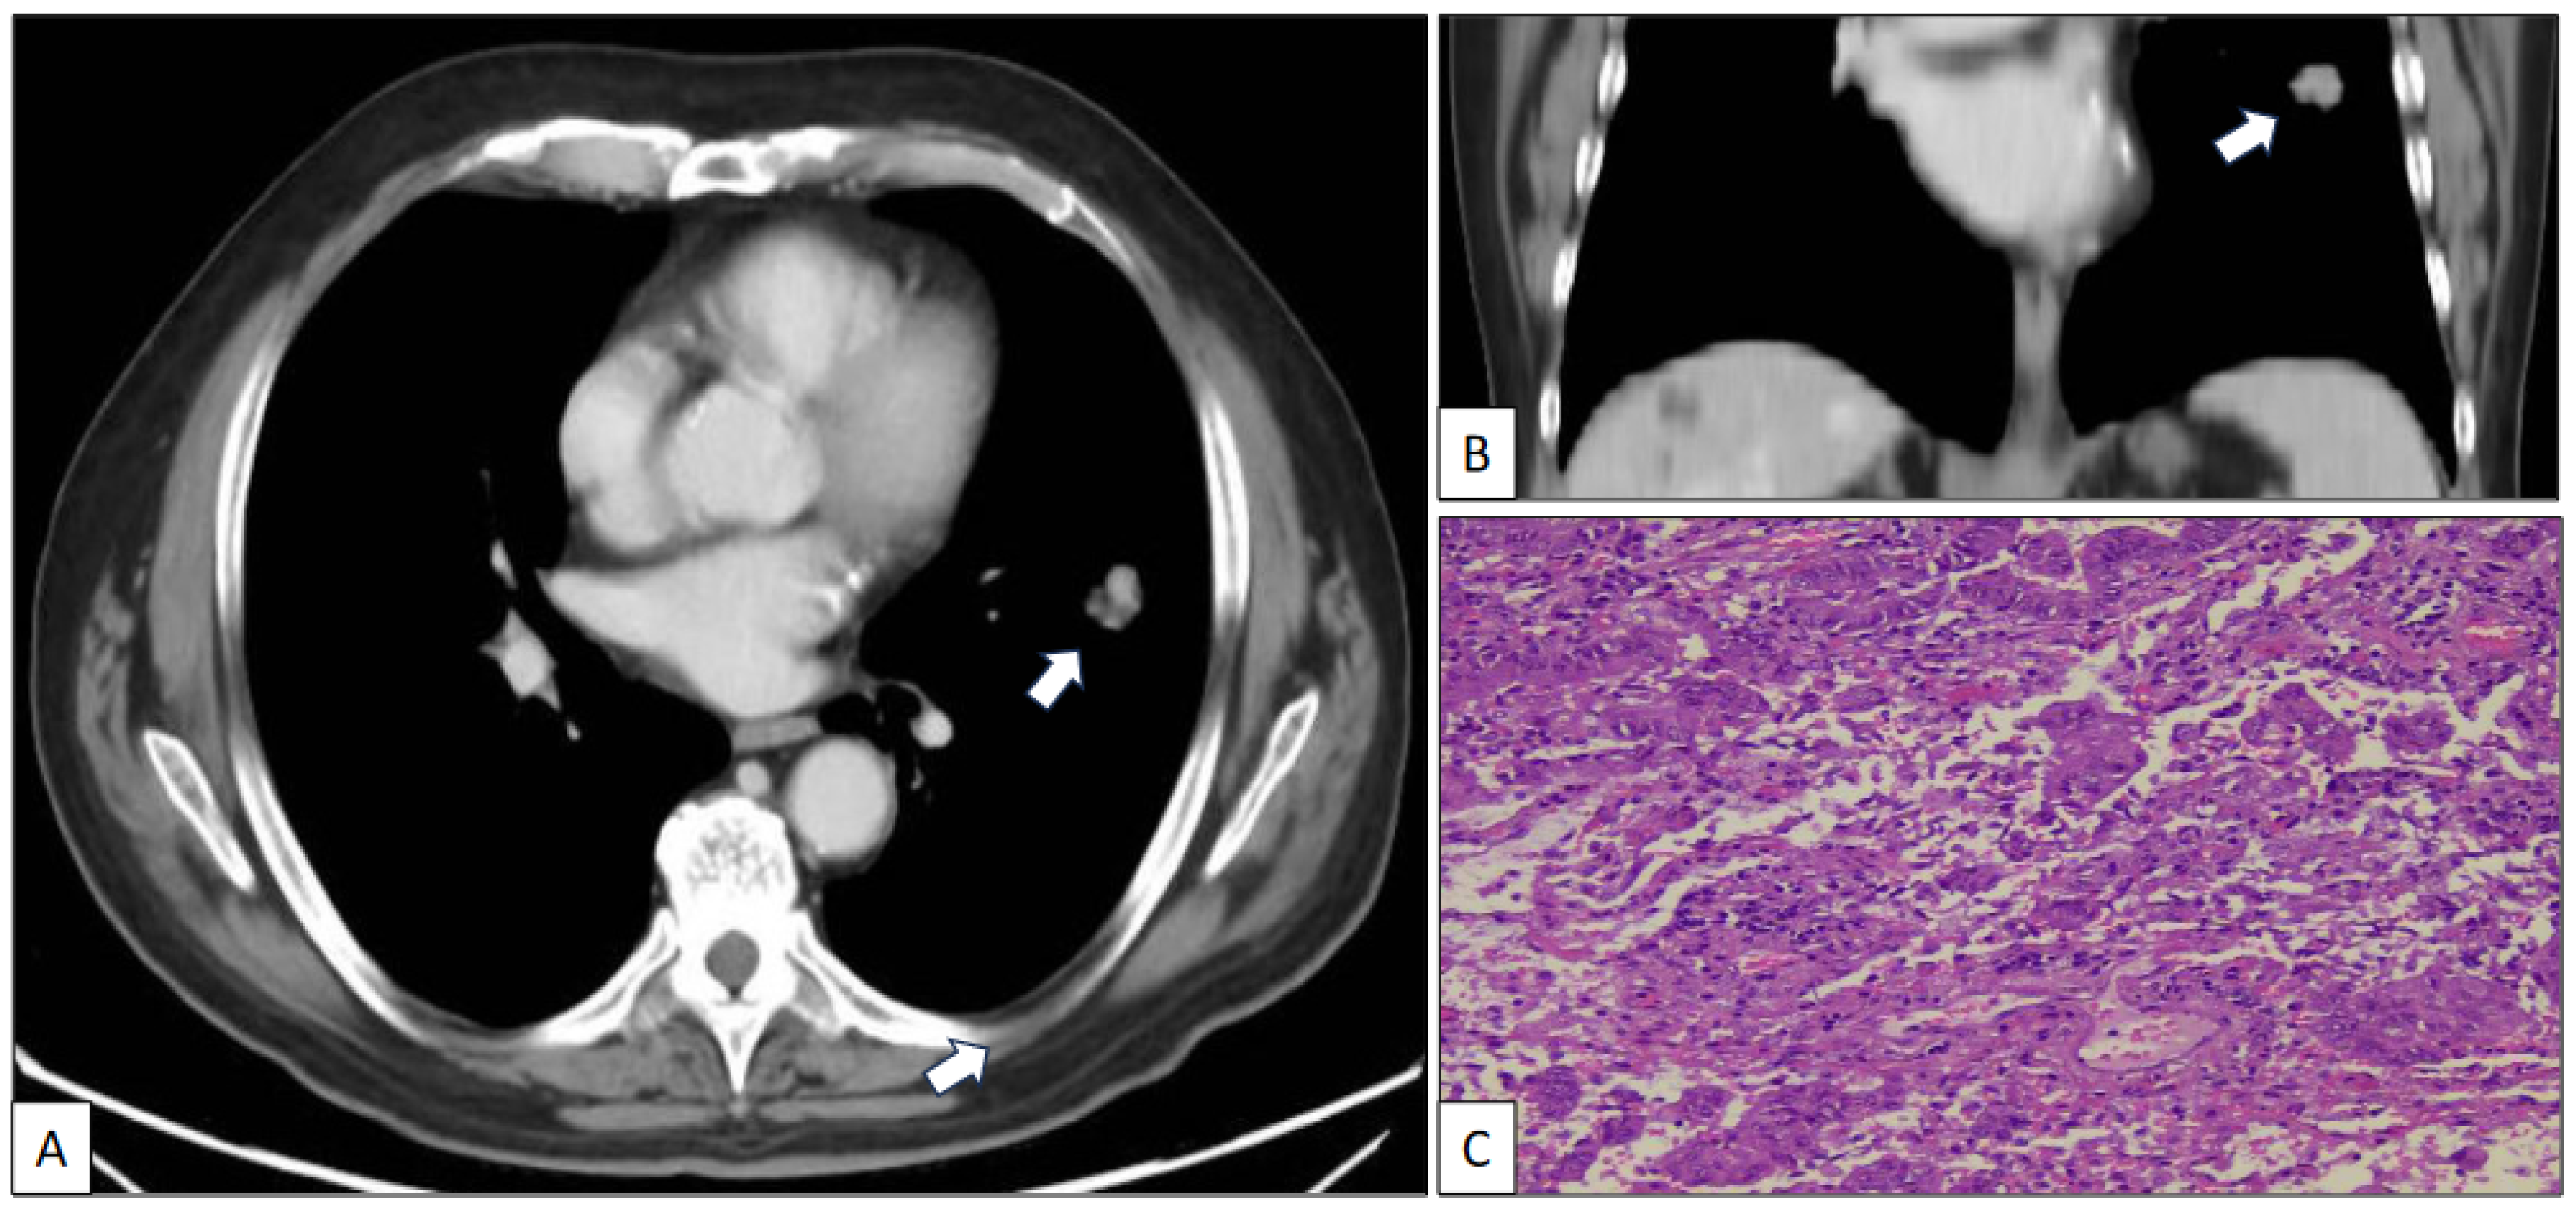

A 73-year-old man with a previous history of severe tobacco smoking (cessation in 1990) and occupational exposure to toxics (automotive tire manufacturing company) underwent an X-ray and CT scan due to persistent cough and fever. The radiological study revealed a 23 mm in diameter irregular nodule located in the left upper lobe (Figure 1A,B). Additionally, a 10 mm in diameter regular nodule with ventilatory impairment was detected in the left lower lobe close to the costophrenic angle (Figure 2). A fine-needle aspiration (FNA) biopsy of the upper lobe nodule yielded a diagnosis of pulmonary adenocarcinoma. A subsequent PET scan indicated a maximum standardized uptake value (SUV max) of 2.59 in the upper lobe lesion and a faint basal uptake value in the lower lobe lesion. The multidisciplinary consensus advised left upper lobectomy plus atypical lung resection in the left lower lobe. The patient is well and free of disease 1 year after the initial diagnosis.

Figure 1.

Axial (A) and coronal (B) CT scan images of a nodule (arrow) in the left upper lobe corresponding to a histologically confirmed pulmonary adenocarcinoma (C) (hematoxylin-eosin, original magnification, ×100).

The left upper lobectomy showed an adenocarcinoma with standard histological features (Figure 1C).